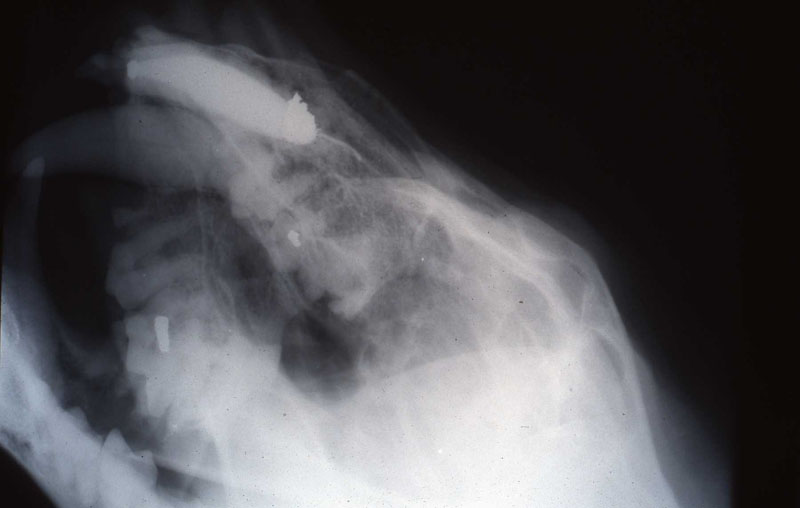

An 18 month old, 7.5 kg , female caracal (Caracal caracal caracal) new to the Milwaukee County zoo collection presented with a fractured right maxillary canine tooth during routine quarantine examination. The canine tooth had approximately 3 mm of its tip fractured off, the pulp chamber was exposed, and the tooth was darkened due to degeneration of of the pulpal tissue, and induction of food debris. There was no sign of an external drainage tract lesion. Radiographic examination revealed the presence of a periapical lesion 6mm by 7mm in diameter. The extra-oral surgical approach was chosen to debride the periapical lesion, resect the apex, and perform a retrograde fill in conjunction with the coronal or oblique endodontic fill.

lnteroperative and postoperative radiographs were obtained to verify endodontic working length and extent of endodontic fill.